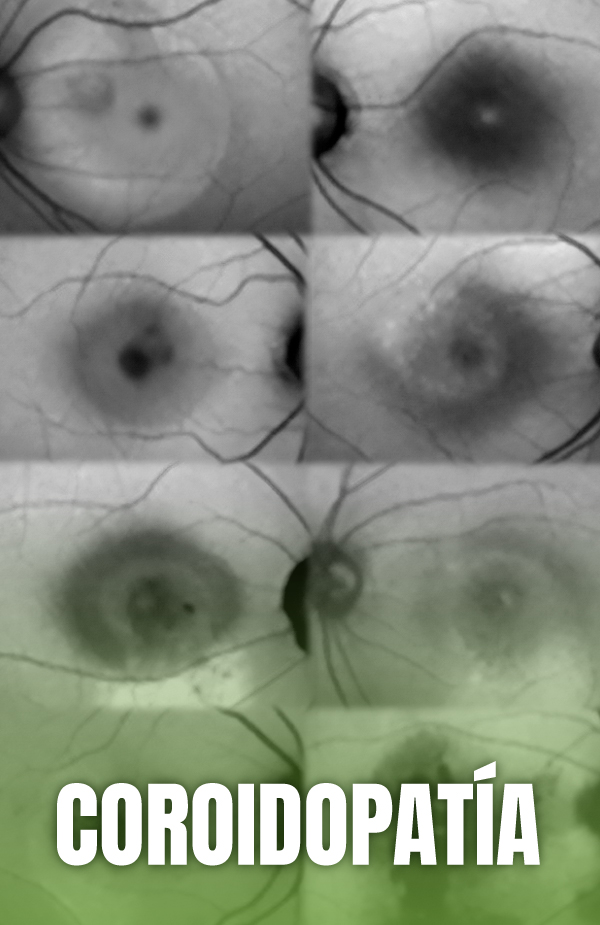

Coroidopatía central serosa: enfermedades del espectro paquicoroideo